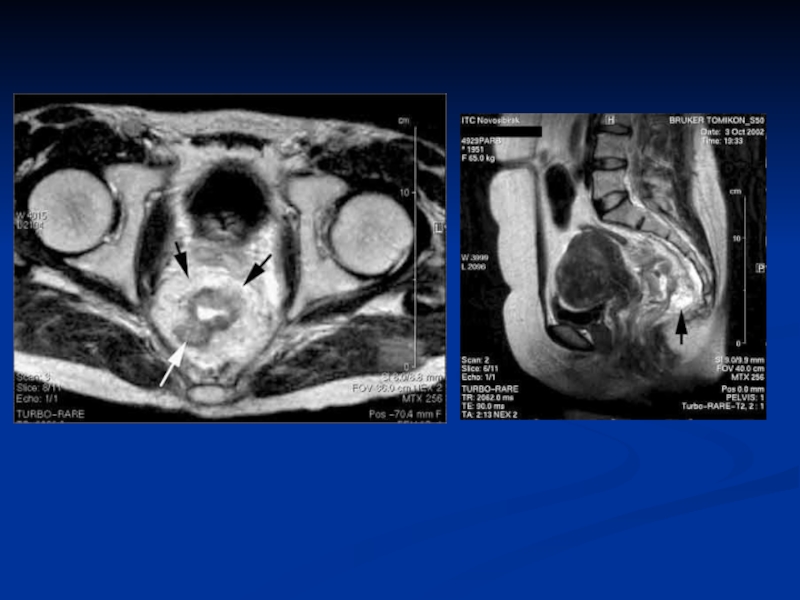

Слайд 62Rectal Cancer

Rectal Cancer